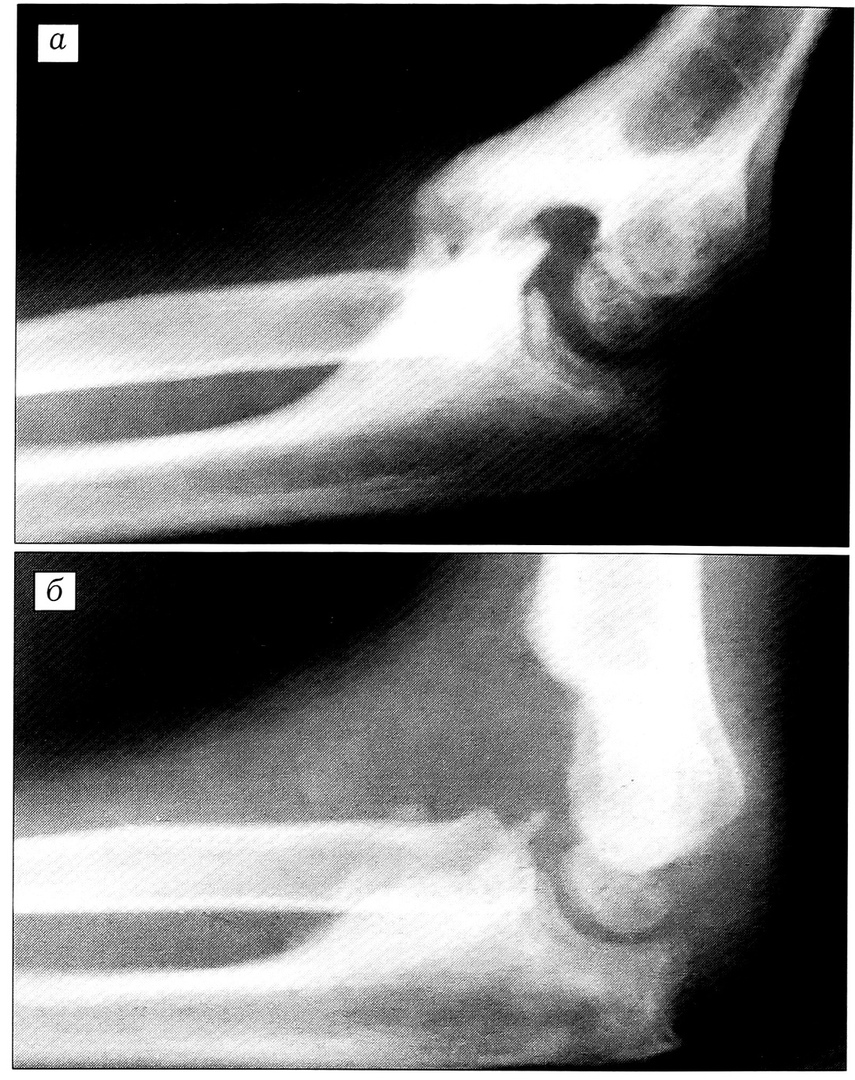

При внесуставном анкилозе у 8 (12,3%) больных произведено удаление оссификата с артролизом и формированием ямок плечевой кости (рис. 1). У 4 (6,1%) больных ямки плечевой кости оказались полностью заполненными костной тканью. У этих пациентов произведено удаление оссификата с формированием «сквозного» канала в дистальном отделе плечевой кости (рис. 2).

Рис. 1. Рентгенограммы локтевого сустава больной У.: а — до операции; б — после операции: удаления оссификата в сочетании с артротомией и формированием ямок плечевой кости.